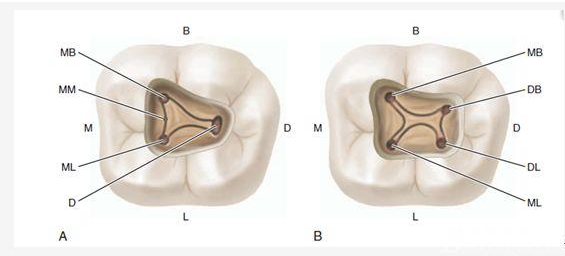

G:找尋MB2的問題:

1、查閱各種文獻,MB2的發(fā)生率在52-96%之間,治療時遺漏是上頜磨牙根管治療失敗的主因,2、一般位于MB1根管口與腭根管口方向的0.5-5mm范圍內,而大多數都位于MB舌側的1-3mm處,其中2mm以內占85.7%,3、MB1-P根管口連線與MB1-MB2根管口的連線夾角大部分(74.3%)在30度以內;4、MB2的尋找大部分需要去除相應部位的牙本質;5、當找到的MB根管口呈“長線型”且有深色凹線向舌側,或者找到的MB根管口明顯偏頰多提示有MB2的可能;6、DOM(牙科手術顯微鏡)的使用有助于找尋MB2;

H、關于下磨牙MM根管的重視問題: